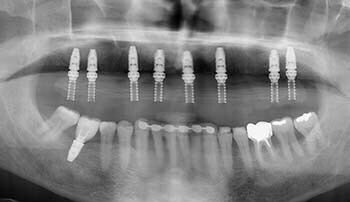

Un guide chirurgical sur mesure va permettre une pose précise de 8 implants 6 mois après le comblement des deux sini maxillaires

Les 8 implants sont posés et l’armature du bridge provisoire est visible sur le cliché panoramique.

Les 6 implants sont posés grâce au guide chirurgical ans décollement des muqueuses, ce qui améliore beaucoup les suites opératoires.

Contrôle de l’ajustage du bridge d’usage sur les piliers.